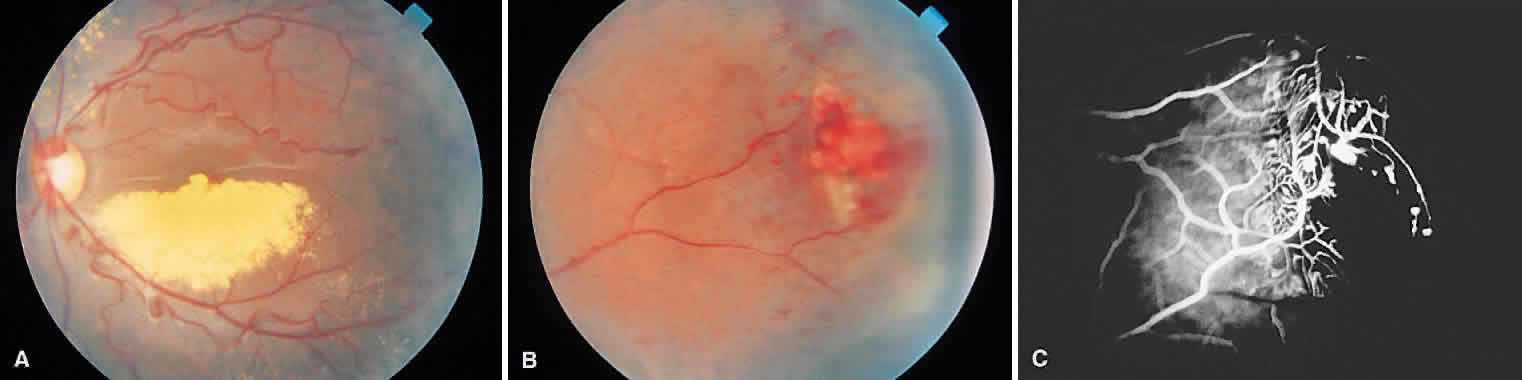

The retinal lesions of angiomatosis retinae are benign vascular anomalies. When the retinal tumor is associated with cerebellar tumors (in approximately 25% of cases), the condition is known as von Hippel-Lindau disease. At a certain stage in the evolution of angiomatosis retinae, the picture is very similar to retinoblastoma (Fig. 9). Both conditions are marked by large feeder vessels that appear to arise de novo in the tumor. When angiomas become gliotic and obscured by overlying detachment, they cannot be clearly differentiated from retinoblastoma. Again, ancillary tests can be useful to detect calcification. When diagnostic difficulty arises and there is no useful vision in the affected eye, the most reasonable course is enucleation.

Fig. 9. A. Capillary hemangioma of the retina with prominent afferent and efferent vessels. B. Fluoroscein angiography showing filling of the tumor with dye. (Courtesy of William Tasman, MD, Philadelphia, PA.)